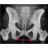

Tunna snitt-serien i 3D-modulen. Vinkla så att bäckenet blir rakt och att symfysen överlappar coccyx och spara en nyckelbild. Både diameter transversa och intertuberavståndet mäts i den sparade nyckelbilden (INTE i 3D-modulen).